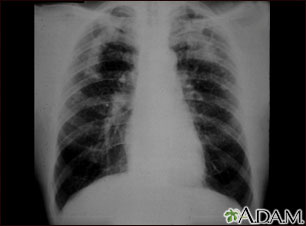

Esta imagen muestra la neumoconiosis complicada del minero. A ambos lados del pulmón hay áreas difusas, pequeñas (de 3 a 5 mm.) y claras. Hay áreas claras grandes junto a los bordes poco definidos en la parte superior de ambos pulmones. Las enfermedades que pueden explicar estos hallazgos en una radiografía son la neumoconiosis complicada del minero (NCM), silicotuberculosis, tuberculosis diseminada, cáncer metastásico de pulmón y otras enfermedades pulmonares infiltrativas difusas.